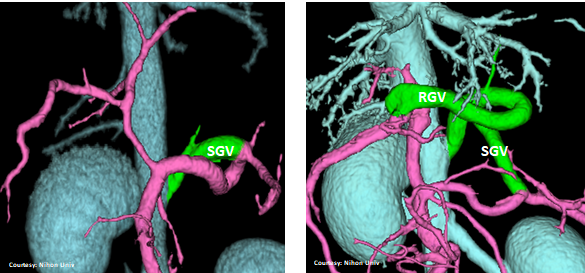

PRE-HEPATIC ENTRANCE

(GSV present)

“LGC +RGV +SGV”

Left Gastro-Caval Shunt with Right Gastric Vein and Short Gastric Vein contributions

Courtesy: Nihon Univ